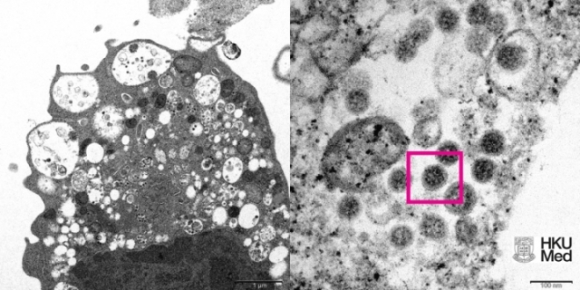

Hình ảnh độ phóng to thấp (trái) và cao của biến chủng Omicron dưới kính hiển vi điện tử. ( Ảnh: HKU)